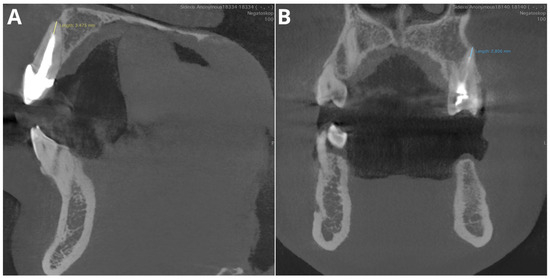

- Overfilling

- Overfilling—examination of any filling material extending beyond the apex of the tooth.